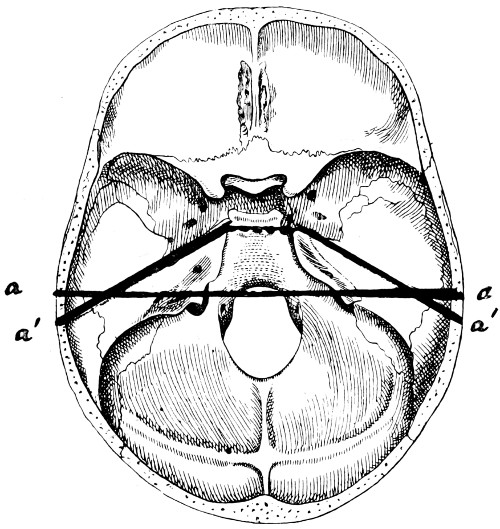

| 29 A and B. The base of the skull and the base as seen on transillumination | 70, 71 |

| 30. Plan of the base of the skull | 77 |

| 31. To illustrate the relation of basic fractures to cranial nerves | 81 |

| 32-37. The lines pursued by basic fractures | 83-8 |